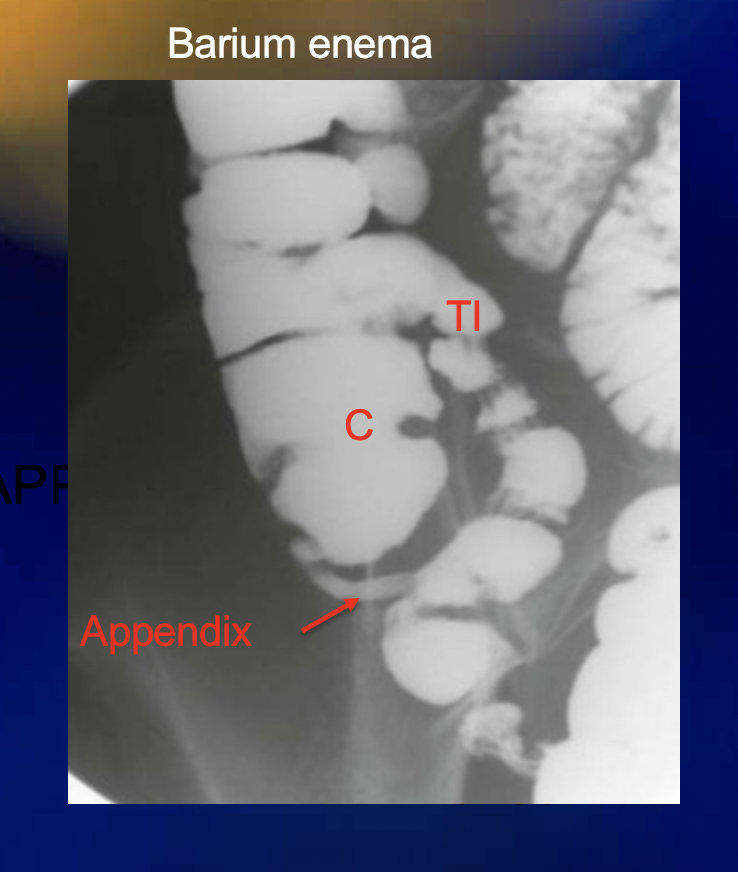

What is the purpose of giving barium sulfate in xray?

What does barium look like on xray or CT?

White

If a person has appendicitis and their appendix is retrocecal, they will likely present with […] pain

If a person has appendicitis and their appendix is pelvic, they will likely present with […] pain

The appendix is [….]peritoneal

Intra